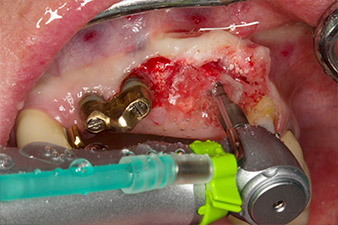

Gewindeschnitt mit dem Winkelstück WS-75 L

Abb. 3: Gewindeschnitt mit dem Winkelstück WS-75 L bei einer Übersetzung von 20:1 (Programm P4). Hilfreich sind hier das hohe Drehmoment des Implantmed, das Hexagon-Spannsystem für sichere Kraftübertragung und die automatische Umkehr der Drehrichtung bei zu hohem Widerstand.

Maschinelles Eindrehen des Implantats

Abb. 4: Maschinelles Eindrehen des Implantats mit dem Winkelstück WS-75 L bei einer Übersetzung von 20:1 (Programm P5).